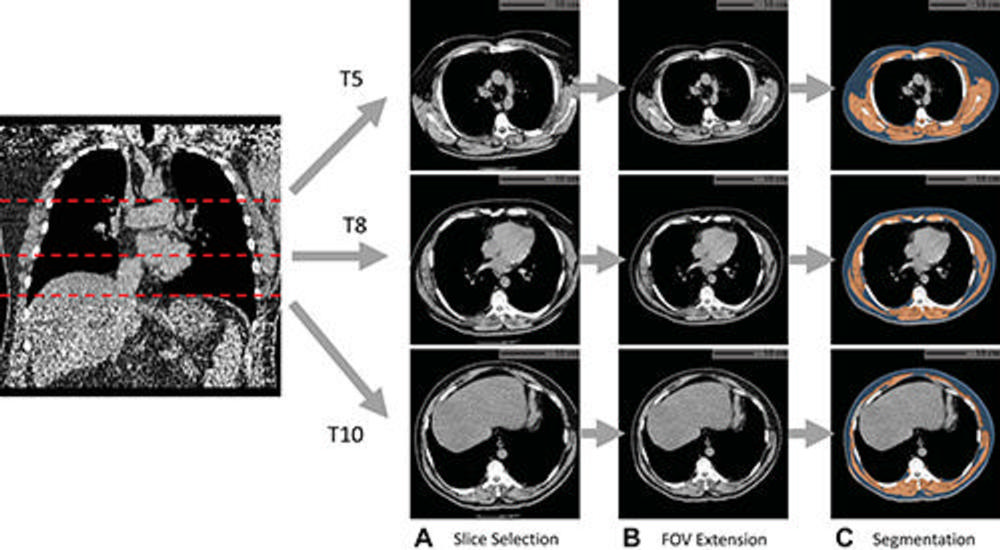

Figure 1. Example of fully automated body composition assessment in the lung cancer screening noncontrast low-dose chest CT scan in a 57-year-old male participant. (A) CT axial plane levels corresponding to the fifth (T5), eighth (T8), and 10th (T10) vertebral bodies were predicted. Corresponding axial CT sections were selected for body composition assessment. (B) The field of view (FOV) of each CT section with body section truncation was extended with missing body section imputation. (C) Areas of subcutaneous adipose tissue (SAT) (blue) and skeletal muscle (SM) (orange) were segmented on the field-of-view extended sections. Body composition measurements include SM index (166.2, normal group), SM attenuation (17.5 HU, lower group), SM SD (41.0 HU, normal group), SAT index (189.7, higher group), SAT attenuation (−88.4 HU, normal group), and SAT SD (28.0 HU, higher group). Indexes were calculated as summed area (in square centimeters) across three levels divided by participant height squared (in square meters).